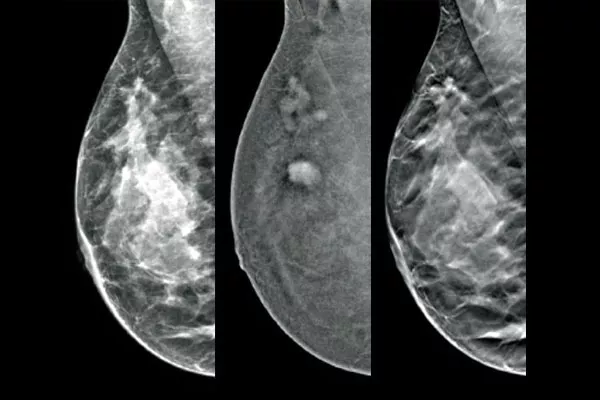

La soluzione Affirm® Contrast Biopsy consente di localizzare e prelevare il tessuto mammario in corrispondenza delle lesioni evidenziate durante la mammografia con contrasto (CEM).Progettata per ottimizzare l'efficienza del flusso di lavoro migliorando al contempo l'esperienza della paziente, la soluzione completa per biopsia con contrasto semplifica la procedura* anche nei casi più complessi.

Procedura stereotassica per localizzare e sottoporre a biopsia le lesioni evidenziate dalla mammografia 2D con mezzo di contrasto, con prestazioni diagnostiche comparabili alla procedura di biopsia mammaria sotto guida RM.1,2 Confronto delle immagini post-marcatore nella stessa modalità dell’esame diagnostico iniziale con contrasto.

Il software per biopsia con mezzo di contrasto consente di sottoporre a biopsia le lesioni identificate durante la mammografia 2D con contrasto I-View™. Sfruttando la capacità di generare immagini 2D, con contrasto e di tomosintesi con un'unica compressione,4 il sistema di guida per biopsia mammaria in posizione verticale Affirm consente di passare rapidamente dalla mammografia alla biopsia, sfruttando la stessa catena di imaging 5 del sistema mammografico per migliorare la visualizzazione 3D™ delle lesioni sospette.**

Il software Affirm® Contrast Biopsy, in combinazione con I-View™ per l'imaging con contrasto e il sistema per biopsia mammaria in posizione verticale Affirm Upright aumenta l'efficienza delle procedure di biopsia mammaria.

L'imaging funzionale con la CEM si dimostra superiore alla risonanza magnetica offrendo una sensibilità comparabile, una specificità maggiore e un valore predittivo positivo più alto. 7,8 Inoltre, rispetto alla RM, la CEM offre un'alternativa più economica 9 e una procedura più breve.7,10